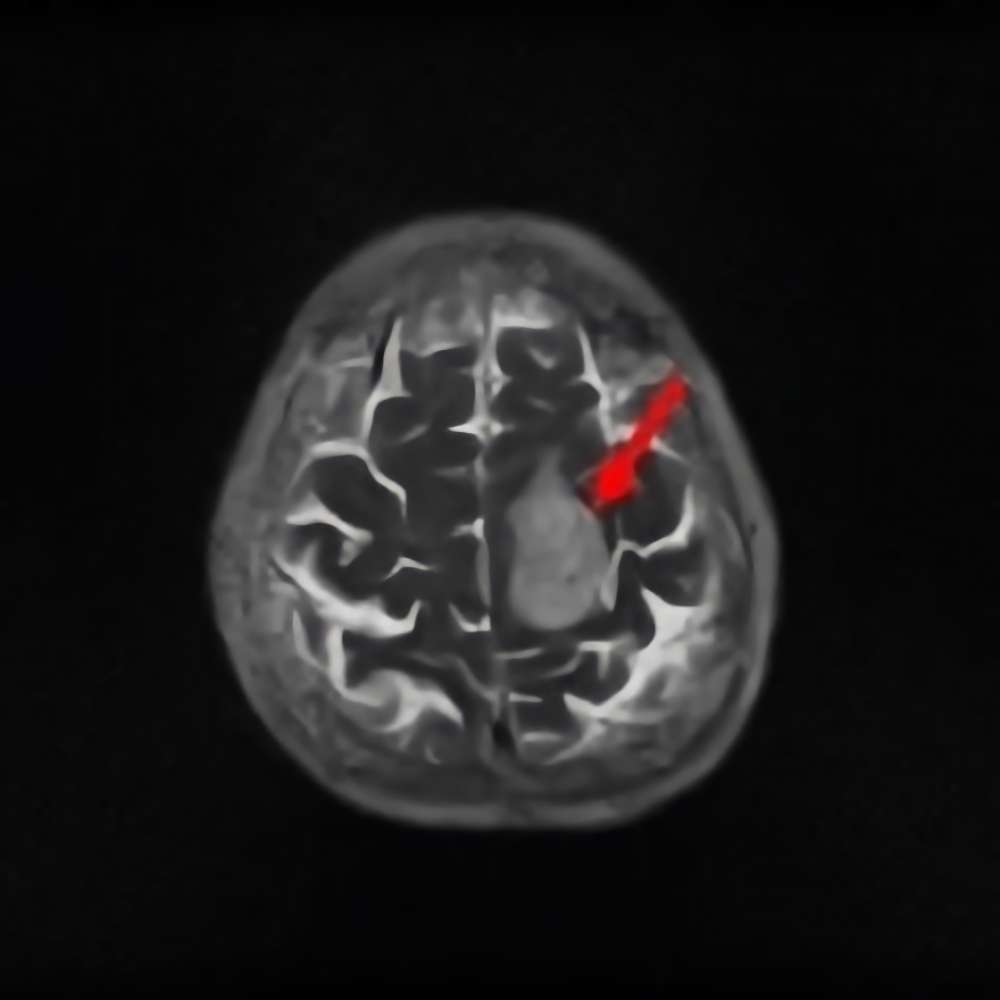

側頭葉膠芽腫

No.’14_167 手術前1

No.’14_167 摘出 前

No.’14_167 摘出 後